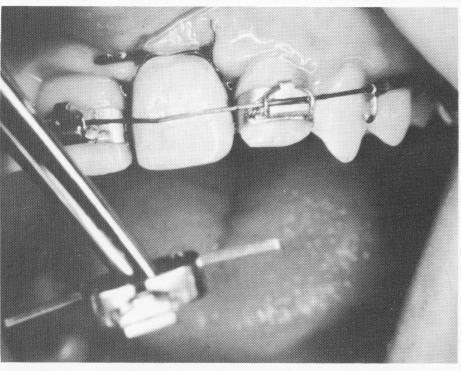

Fig. 15-97. A band containing a labial bracket and two rigid lingual arms was fitted to the left central incisor. (From Linkow, L. I.: The endosseous blade implant and its use in orthodontics, Int. J. Orthodont. 8 [4] :149-154, 1969.)